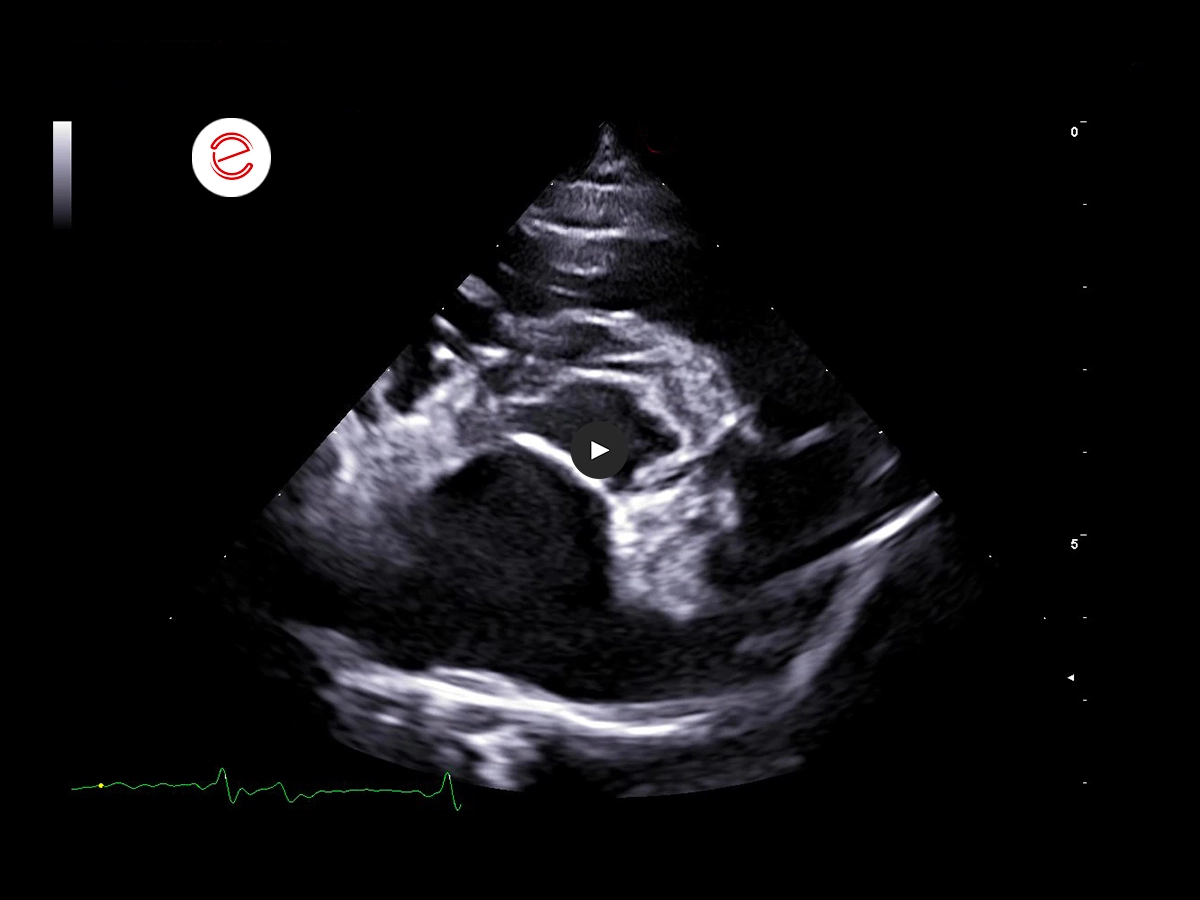

On the right parasternal long-axis 5-chamber view, these echogenic parallel lines within the dilated pulmonary artery are highly suggestive of the presence of adult Dirofilaria immitis.

On the right parasternal short axis view at the heart base, echogenic parallel lines suggestive of adult Dirofilaria immitis are seen within the main pulmonary artery and right ventricular outflow tract.